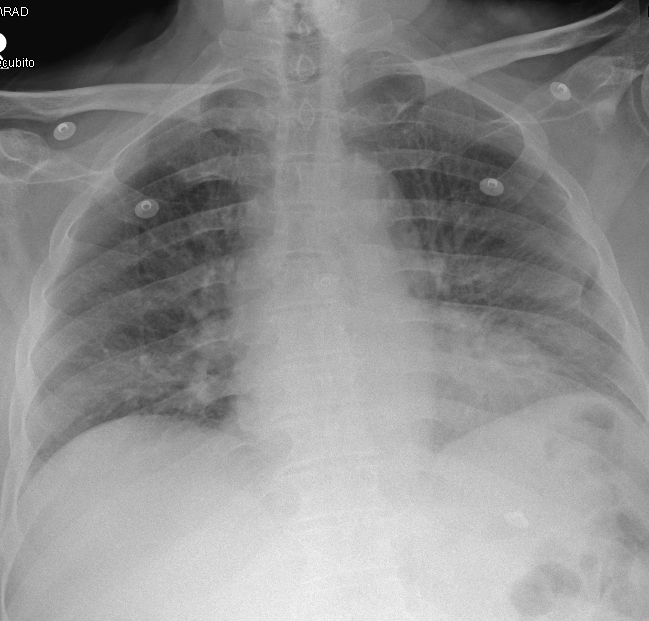

Radiografía de tórax: pérdida de volumen pulmonar con elevación de hemidiafragma derecho (imagen 1), no presente en previas (imagen 2). No claros infiltrados ni derrame pleural.